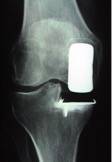

La PUC (Prothèse Uni Compartimentaire)

Son indication est l’arthrose isolée d’un compartiment du genou (interne ou externe) avec une intégrité du ligament croisé antérieur et l’absence d’arthrose fémoro patellaire.

Cette prothèse ne permet pas le ‘redressement de la jambe ‘ : elle ne permet que la compensation de l’usure cartilagineuse.